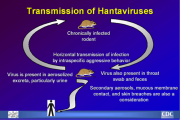

| 13:06, 17 במרץ 2024 | Hanta 2.png (קובץ) |  |

165 קילו־בייטים | Motyk | 1 | |

| 13:02, 17 במרץ 2024 | Hanta 1.png (קובץ) |  |

224 קילו־בייטים | Motyk | 1 | |